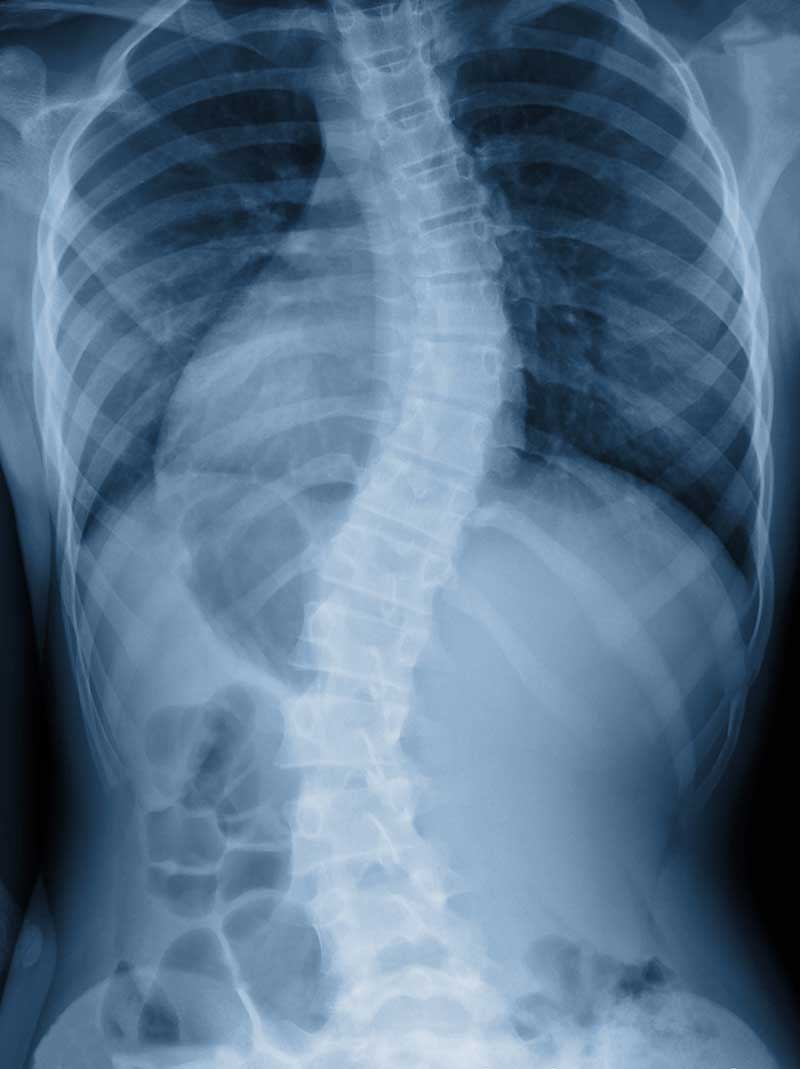

Scoliosis

When detected early, scoliosis can be managed and treated to prevent the problem from getting worse. With scoliosis, the spine has abnormal curvatures to the side or even twists. Most cases of scoliosis appear for unknown reasons as scoliosis tends to develop before puberty in adolescence, in children who previously had no spine issues.

Many cases of scoliosis do not require surgery or extensive treatment, but if the curvature becomes more severe, medical intervention may be needed. Scoliosis appears equally in boys and girls, but typically girls are more likely to develop significant curvature that warrants treatment.